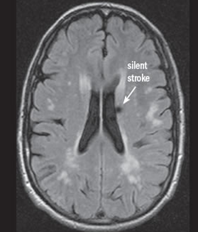

Deși unele tipuri de infarct sunt aparente pentru ochiul liber neprofesionist (Fig.2), altele sunt mai subtile și mult mai reduse în intensitatea aparentă și dimensiune (Fig.3 & Fig.4).

În imaginile din figurile 2-4 se pot vedea cu ochiul liber abnormalitățile la nivelul creierului din imaginile RMN. Astfel de cazuri reprezintă o parte importantă din setul de date, iar restul imaginilor e compus din cazuri mult mai greu de identificat sau clasificat chiar și pentru radiologii cu experiență. Pentru moment suntem departe de a concura cu precizia și acuratețea radiologilor, dar soluțiile de detecție automată de astfel de leziuni vor să vină în ajutorul medicilor. Un medic radiolog interpreta în jur de 679 imagini de tip RMN per zi în anul 2010 [9]. De atunci cantitatea de imagini produse de aparatura medicală e în continuă creștere iar presiunea asupra radiologilor crește și ea, iar cu aceasta cresc și șansele de eroare sau de ratare a unor leziuni importante. O soluție automată vine ca un adjuvant pentru radiolog asigurându-se că acestuia nu îi scapă niciun caz clar de leziune, iar radiologul se poate axa pe cazurile cu adevărat dificile și importante. Și în plus, un algoritm nu suferă de oboseală și nici nu necesită repaus.

Fig. 2 a) Simulare detecție de infarct cerebral acut din RMN-DWI. Ref: [6]